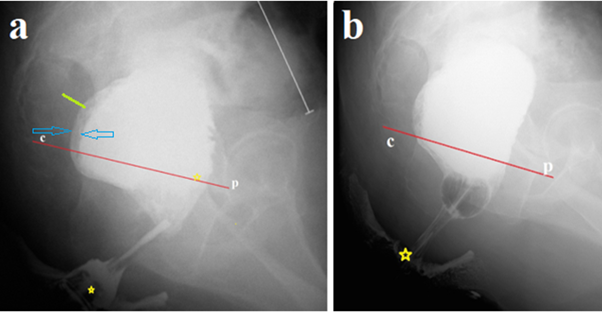

In our case, the perineum in front and behind the anus was smeared with barium paste to determine the location of the anus as the point of intersection of the enema tip with the contrast line on the perineum. 300 ml of barium suspension was injected into the rectum (Figure 1a). After removing the enema tip, a No. 20 Foley catheter was inserted into the rectum without any effort. The balloon was inflated to a diameter of ≈ 2.5 cm and pulled into the anal canal as far as it would go. The balloon stopped over the constriction at 1.9 cm from the anus (Figure 1b).

Figure 1 The study was carried out after colon cleansing. (a). A lateral radiograph of the anorectum was taken after administration of 300 ml of barium. It is known that the true length of the anal canal between the anus and the pubococcygeal line (p-c), i.e., between two yellow stars, is 4 cm. The tone of the rectum is increased, as evidenced by the expansion of the retrorectal space (green line - 0 .8 cm) and barium in the folds of the mucosa between the blue arrows. The presence of barium below the p-c line indicates insufficiency of the puborectalis muscle (descending perineal syndrome). The sigmoid colon (white line) is significantly dilated to 4 cm (b). The Foley catheter balloon, inflated in the rectum to a diameter of ≈ 2.5 cm, became lodged in the anal canal above the stenosis, 1.9 cm from the anus.